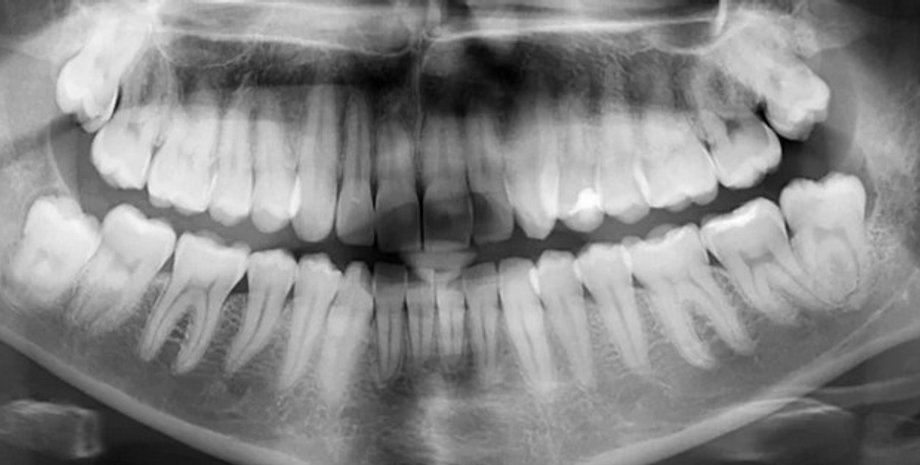

У 25% людей на Земле отсутствует хотя бы один зуб мудрости | Фото: ScienceAlert

Зубы мудрости представляют собой третий набор коренных зубов, расположенный в самой задней части человеческого рта. Они выглядят также, как и другие моляры, однако иногда могут быть меньшего размера, пишет IFLScience.

Эти зубы получили свое название из-за того, что появляются последними из 32 постоянных зубов, как правило, это происходит в возрасте от 17 до 25 лет, когда человек становится старше и мудрее. Однако известно, что далеко не у всех людей на планете появляются все четыре зуба мудрости — статистика свидетельствует о том, что четверть людей на Земле лишены хотя бы одного из этих зубов.